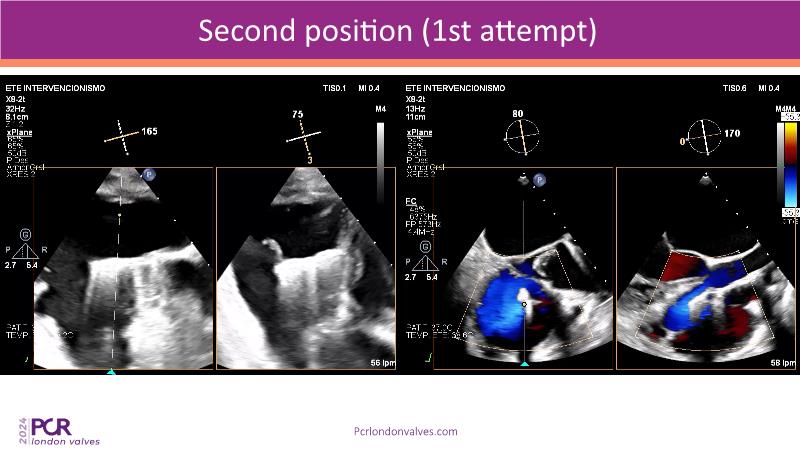

This session examines two compelling cases: a 78-year-old woman with paroxysmal atrial fibrillation, chest trauma, an osteoporotic sternum fracture, and NYHA II exertional dyspnoea, and an 82-year-old man with chronic three-vessel coronary artery disease, bradycardic AF, peripheral arterial disease, spinal stenosis, and chronic kidney disease. Through their study, discover the intricate anatomy of atrioventricular valves, the therapeutic challenges they pose, and the growing significance of transcatheter edge-to-edge repair (TEER) therapies. The discussion also highlights the value of multidisciplinary strategies in managing complex valve diseases effectively.